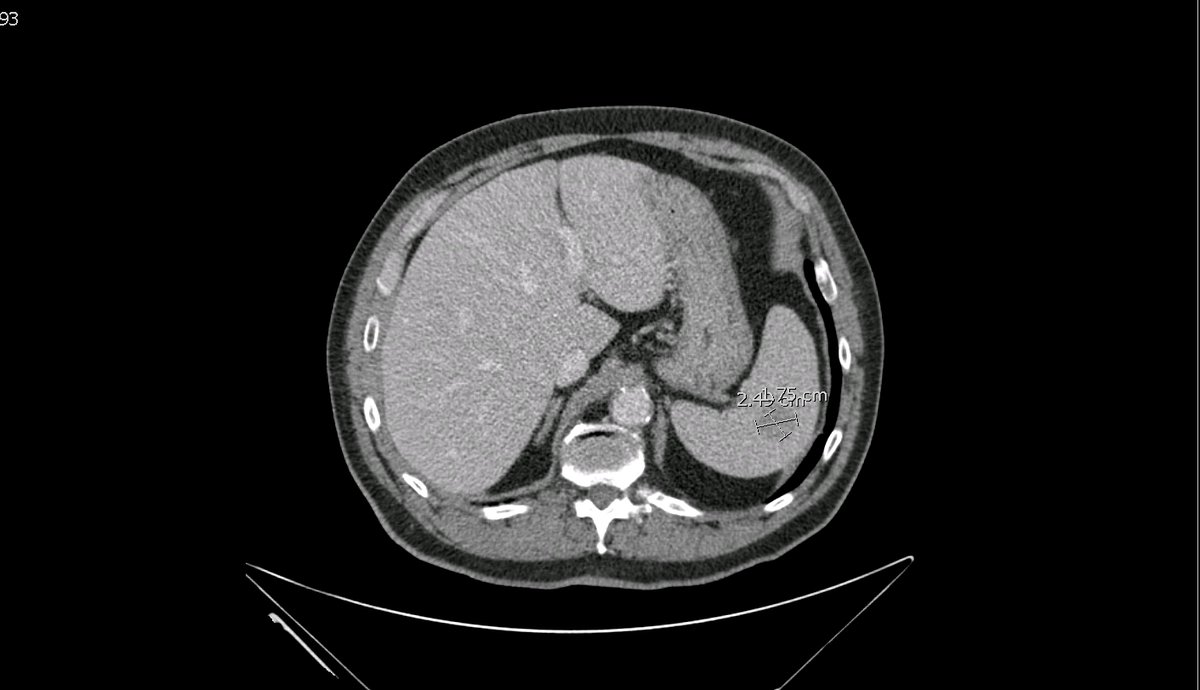

New study @AnnalsofIM bit.ly/2Km3KYu by @DrTalenfeld @WeillCornell: Percutaneous ablation for T1a #renalcancer has similar 5-year survival rates to radical nephrectomy but with far fewer 30-day complications and less #kidneyfailure.